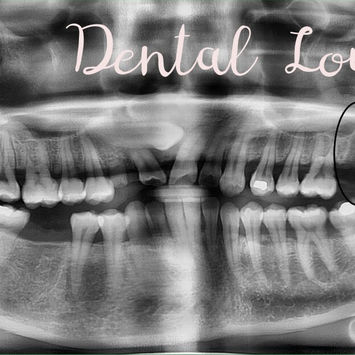

Fractured, 3-rooted with long, wide, flattened MB and DB roots

Additional CBCT Findings

Buried retained #11

Exposed and deviated #13 crossing the root of erupted #12

Left maxillary sinus: high fluid level + blocked nose

Possible left maxillary sinusitis (KIV)